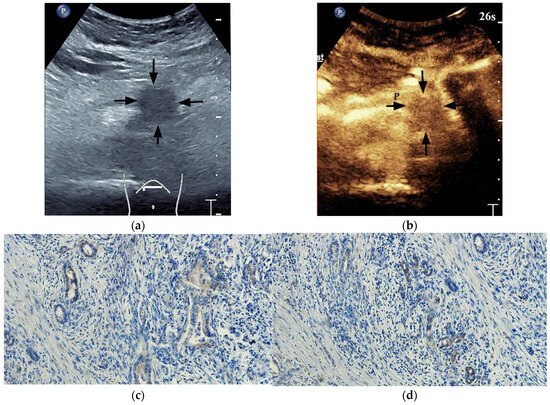

A quantitative analysis of CEUS was performed using the Software VueBox Quantification Toolbox (version 4.3). A total of 72 of 102 lesions obtained the ROIs parameters. Among the 72 cases of PDAC, 24 cases showed both high HIF-1α and GLUT1 high expression, 21 cases showed both low HIF-1α and GLUT1 low expression, 12 cases showed high HIF-1α but GLUT1 low expression, and 15 cases showed low HIF-1α but GLUT1 high expression. Both HIF-1α-high PDACs and GLUT1-high PDACs showed higher peak enhancement (PE) (p = 0.024 and p = 0.018, respectively) (Figure 5 and Figure 6) and higher wash-in rate (WIR) values (p = 0.015 and 0.002, respectively) (Table 5) more frequently. There were no significant differences in rise time (RT), time to peak (TTP) and wash-in area under the curve (WiAUC) between HIF-1α or GLUT1 high and low expression PDACs (p > 0.05 for all).

Figure 6. A 69-year-old male patient with a pancreatic ductal adenocarcinoma. (a) US revealed a hypoechoic lesion (arrows) at the pancreatic head. (b) The lesion (arrows) demonstrated hypo-enhancement on CEUS. (c) Time intensity curve analysis demonstrated a relatively lower peak enhancement value (5420 [a.u.]). (d) Photomicrographs of immunohistochemistry stain sections demonstrate a HIF-1α low expression ductal adenocarcinoma (original magnification, ×200). (e) Photomicrographs of immunohistochemistry stain sections demonstrate a GLUT1 low expression ductal adenocarcinoma (original magnification, ×200).